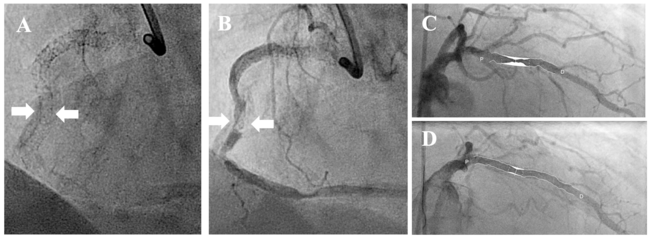

Patient selection and study design. The present study is a non-randomized prospective registry. Patient recruitment took place in the Heart Centre Trier and the German Heart Centre, Technical University, Munich between November 2019 and September 2021. During this period, 3244 patients underwent percutaneous coronary intervention (PCI) in both centers. A total of 561 lesions (17.3%) were ISR. In 117 patients (3.6%), the ISR was graded as calcified. In 81 patients (2.5%), angioplasty was performed using CB or SB angioplasty. All these patients had angiographically calcified ISR (Figure 1) and the calcification was graded into moderate or severe, as previously described.13-15 It was recommended to perform intravascular imaging. The decision whether and which intravascular imaging method was used was the responsibility of the operator.

Quantitative coronary angiography. We performed offline quantitative coronary angiography (QCA) in all patients. The QCA was evaluated as previously described.13,16 In brief, the analysis was performed before CB or SB dilatation and at the end of the procedure (Figure 1A-C). The stenoses were categorized as eccentric or concentric. The severity of calcification was assessed using angiographic criteria as previously described.13,16 In brief, a moderate calcification was assumed if the calcification was only seen during the cardiac cycle. If the calcification was visible even without cardiac motion, it was classified as severe. Treatment success (primary endpoint) was achieved if a residual stenosis of less than 20% was present in the QCA. Strategy failure was present if the residual stenosis in the QCA was greater than 20% (Figure 1D).